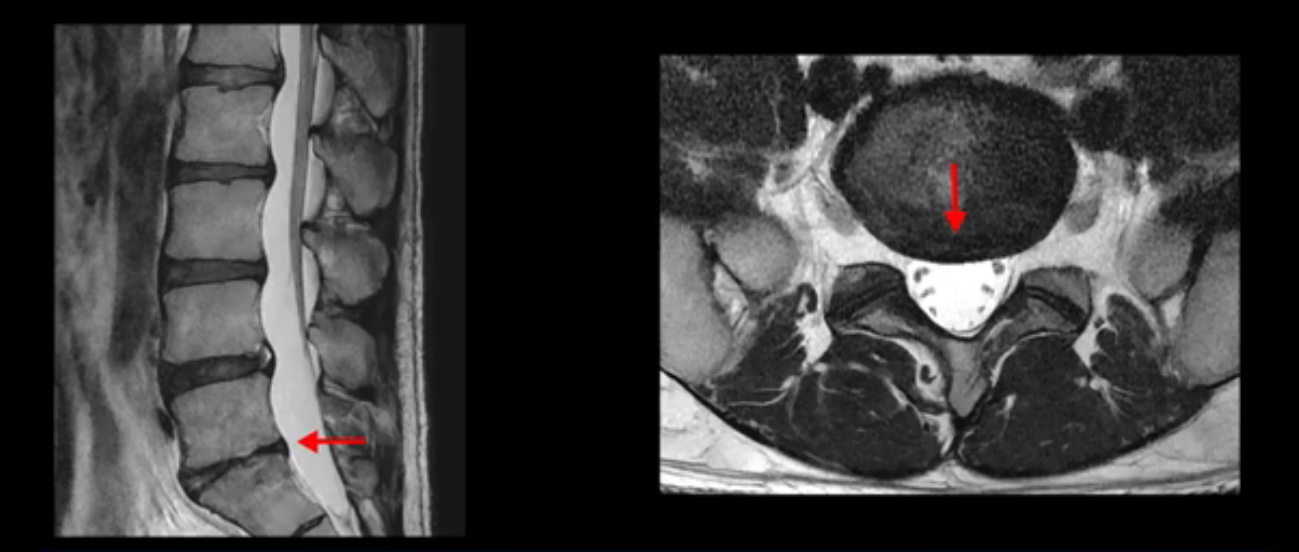

4번 5번은 가운데로 섬유륜이 찢어져서 디스크가 살짝 밀려나와 있지만 역시나 최근에 찢어지고 밀려나온 걸로 판단되지 않고 오래 전에 찢어진 흔적으로 보입니다.

앞서 1번 2번, 4번 5번, 5번 1번의 디스크가 찢어지고 조금 밀려 나온 게 최근에 찢어진 게 아니고 오래된 걸로 보인다고 말씀 드렸죠. 왜 그럴까요? 만약 급성으로 찢어진 것이라면 아주 심한 디스크성 통증이 있겠죠. 기침이나 재채기를 하면 심하게 아프고 허리를 조금만 구부리거나 비틀면 아주 날카로운 통증들이 생길 겁니다. 그런데 이분은 이런 증상이 전혀 아닙니다. 또 디스크의 밀려나온 정도도 전혀 심하지 않기 때문에 이분이 가지고 계신 양쪽 다리 저림, 특히 이분은 누워있을 때도 양쪽 발이 발가락까지 쑤신다고 하는데 이정도 디스크 때문에 그런 증상은 생길 수가 없는 겁니다. 이처럼 이분의 가벼운 디스크 탈출은 이미 오래 전에 진행되었고 섬유륜 자체는 이미 아문 상태인데도 디스크내장증을 진단받은 환자들 중에는 본인이 섬유륜 파열 환자라고 끝까지 믿는 분들이 많습니다. 다시 말하지만 디스크내장증이라는 진단을 받은 환자들을 보면 거의 전부 다 섬유륜 파열 증상이 아닙니다. 증상이 완전히 다릅니다. 진단이 애초에 잘못되면 어떤 치료를 받아도 좋아질 수 없습니다.

이분은 어떤 한 병원에서 디스크 내장증 얘기를 들으셨는데요. 여기 보시는 것처럼 4번 5번의 하얀 HIZ(High Intensity Zone)을 보고 디스크 내장증의 근거로 얘기하는 병원들이 있는데,

이 HIZ는 섬유륜이 찢어졌다가 이미 아문 뒤에도 얼마든지 보일 수 있는 흔적일 가능성이 있어서 재채기를 하면 아픈지, 허리를 구부릴 때 날카로운 통증이 생기는가 등의 증상으로 구별해야 하는데 MRI만 보고 HIZ가 보이면 그게 마치 통증의 원인인 것처럼 얘기하는 의사들이 있습니다. 이분 MRI를 자세히 보고 증상을 정말 자세히 들어본 의사가 있었더라면 다른 환자분들처럼 증상과 MRI가 일치하지 않는다는 얘기를 들을 수 있었을 텐데 이분은 그런 얘기는 듣지 못했습니다.